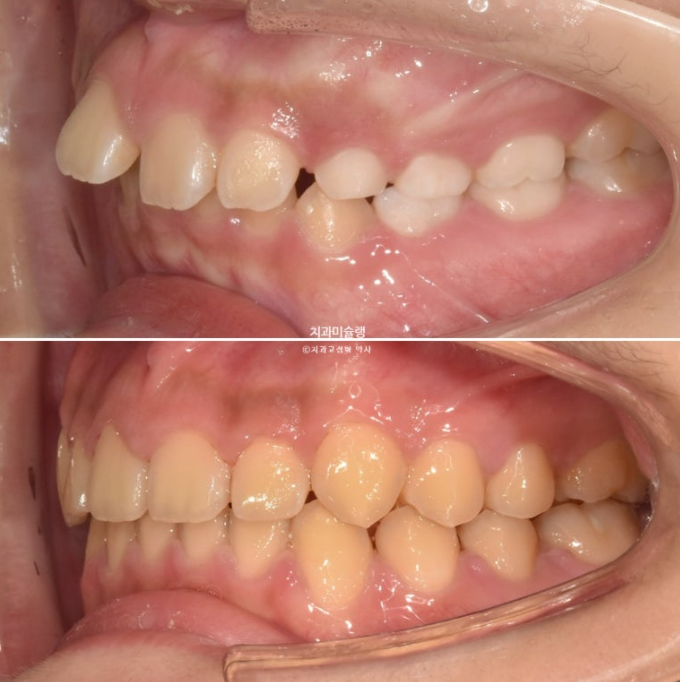

이제 어린이 교정 전후비교 보겠습니다

총 치료기간은 1년 9개월 그 중 중간에 영구치 맹출을 기다리는 시간 6개월을 제외하면 액티브하게 장치를 낀 시간은 1년 3개월 입니다.

23.11-25.08

23.11~25.08

윗니 아랫니 간격 차이가 줄며 입 다무는 게 편해집니다.

이 나이대 친구들이 앞니 돌출 때문에 입 벌리고 자는 습관이 생기면 구호흡에 의한 여러가지 부작용이 생깁니다.

얼굴이 길게 자라거나 입냄새가 나거나 충치가 잘생기거나 등

돌출입 성인되서 발치하고 교정해야겠다.

라는 생각보다는 미리미리 교정하는 게 좋습니다.